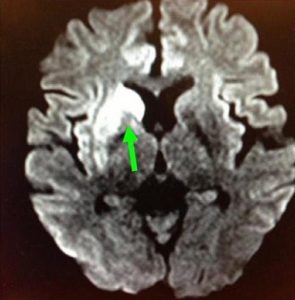

羅先生被送往私家醫院的第一步是進行緊急磁力共振造影,報告顯示羅先生右邊頸和腦部血管大動脈全部都被血栓堵塞着,右邊大腦缺血水腫,導致左邊手腳冇力和神智半昏迷。經過腦血管外科醫生的診斷和急救,在全身麻醉下,醫生使用尤如髪絲微細的導管,經過病人右邊大腿的腹股溝的大動脈而入,導管再經過腹部和胸腔的大動脈一直向上,遊走到病人右邊的頸和腦部血管大動脈,進行機械式血栓吸取內血管治療急救。

手術成功 患者手腳活動能力恢復